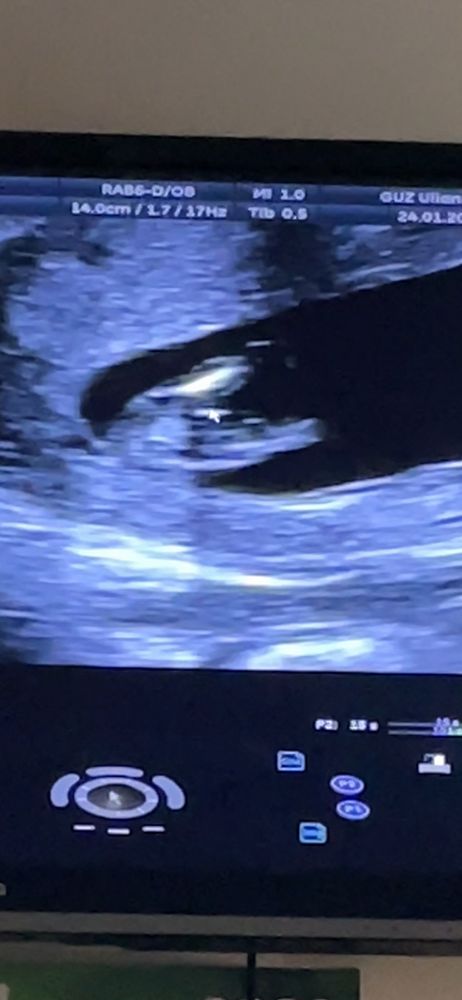

Чашка утреннего кофе, да, 13 недель , врач на 3 фото сказал торчит как у пацана) но я не верю)

кажется мальчик....

у девочки прям отчетливая петелька... на последнем фото из-за стрелки плохо видно

А я не могу никак определять по бугорку)) но так удобненько лежит, прям мужчина 😃